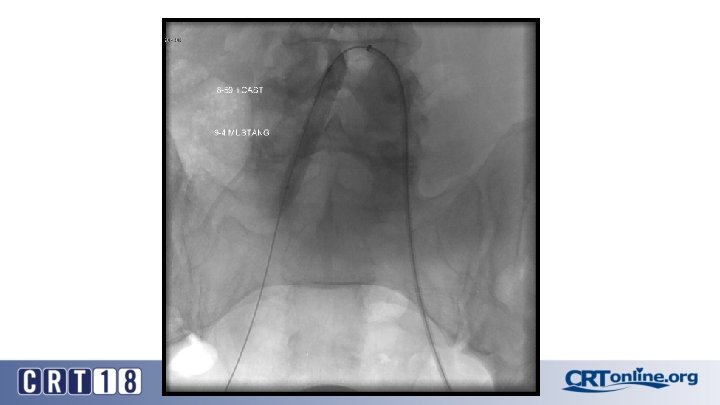

CS Compared to BMS in iliac occlusion • 2009 and December 2015, 128 iliac artery occlusions were stented • A CS was implanted in 78 iliac arteries (61%) and a BMS in 50 (49%) • After propensity score matching (lesion site and length separated and associated femoropopliteal disease included) (47 for each group). • Technical success was 98% • Complication rates same: 12% vs. 12%, p = 1. 0 • 30 day mortality rates same: 2% vs. 2%, p = 1. 0 Piazza M, et al. Outcomes of polytetrafluoroethylene-covered stent versus bare-metal stent in the primary treatment of severe iliac artery obstructive lesions. J Vasc Surg. 2015; 62(5): 1210 -8.

CS superior to BMS, in the right setting • At 36 months (average 23 ± 17) overall primary patency only approached significance: 87% vs. 66%, p =. 06 • For TASC D, CS: 88% vs. BMS: 54% (p =. 03) • Patency was in favor of CSs for occlusions > 3. 5 cm in length (p =. 04), total lesion length > 6 cm (p =. 04), and occlusion with calcification > 75% of the arterial wall circumference (p =. 01) • Kissing stent patency also superior with CS